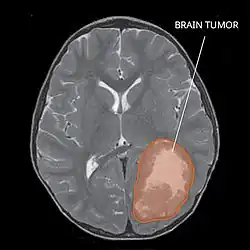

| Primitive neuroectodermal tumor of the central nervous system in a 5-year-old |

The rate of PNETs in not correlated with sex, but it shows a correlation with age.[1] Most cases occur in children around 5 years of age, having a very low frequency in adults.[1] Regarding genetic mutations, a specific type of gene alteration that directly leads to this tumor hasn't been defined yet.[1] However, a positive correlation between individuals with Li-Fraumeni syndrome with a mutation in the gene p53 and PNET has been reported.[2] A significant number of individuals with mutations on the rb tumor suppressor gene have also developed the tumor.[2] Such gene encodes for the protein Rb responsible for stopping the cell cycle at the G1 phase.[6] Another possible contributing factor are mutations in the CREB-binding protein, whose function includes activating transcription,[6] but this interaction still need to be studied further.[2] It has also been presumed that the tumor can arise from cranial irradiation.[2]

Most children that develop primitive neuroectodermal tumors are diagnosed early in life, usually at around 3–6.8 years of age.[2] Symptoms patients present at time of diagnosis include irritable mood, visual difficulties, lethargy, and ataxia.[2] The circumference of the patient's head might also become enlarged and they might be subject to seizures, especially if they have less than one year of life.[2]

Several analysis can be used to determine the presence of the disease. Physical examinations showing papilledema, visual field defects, cranial nerves palsy, dysphasia, and focal neurological deficits are evidences for possible tumor.[2] PNETs can also be spotted through computed tomography (CT) and magnetic resonance imaging (MRI).[2] In images produced by MRIs, an irregular augmentation among a solid mass will indicated the presence of tumor.[3] However, the results of MRIs are usually ambiguous in defining the presence for this specific tumor.[2] In CT scans, the presence of PNETs will be indicated by an elevated density and an increase in volume of the brain.[2] The CT scan can also show calcification,[3] which is present in 41-44% of PNET cases.[2] Since the tumor can be replicated in other parts of the nervous system through the cerebrospinal fluid (CSF), a CSF analysis can also be conducted.[2] A spinal MRI is a fourth type of analysis that is useful in investigating the level of tumor propagation to the spinal cord.[2]